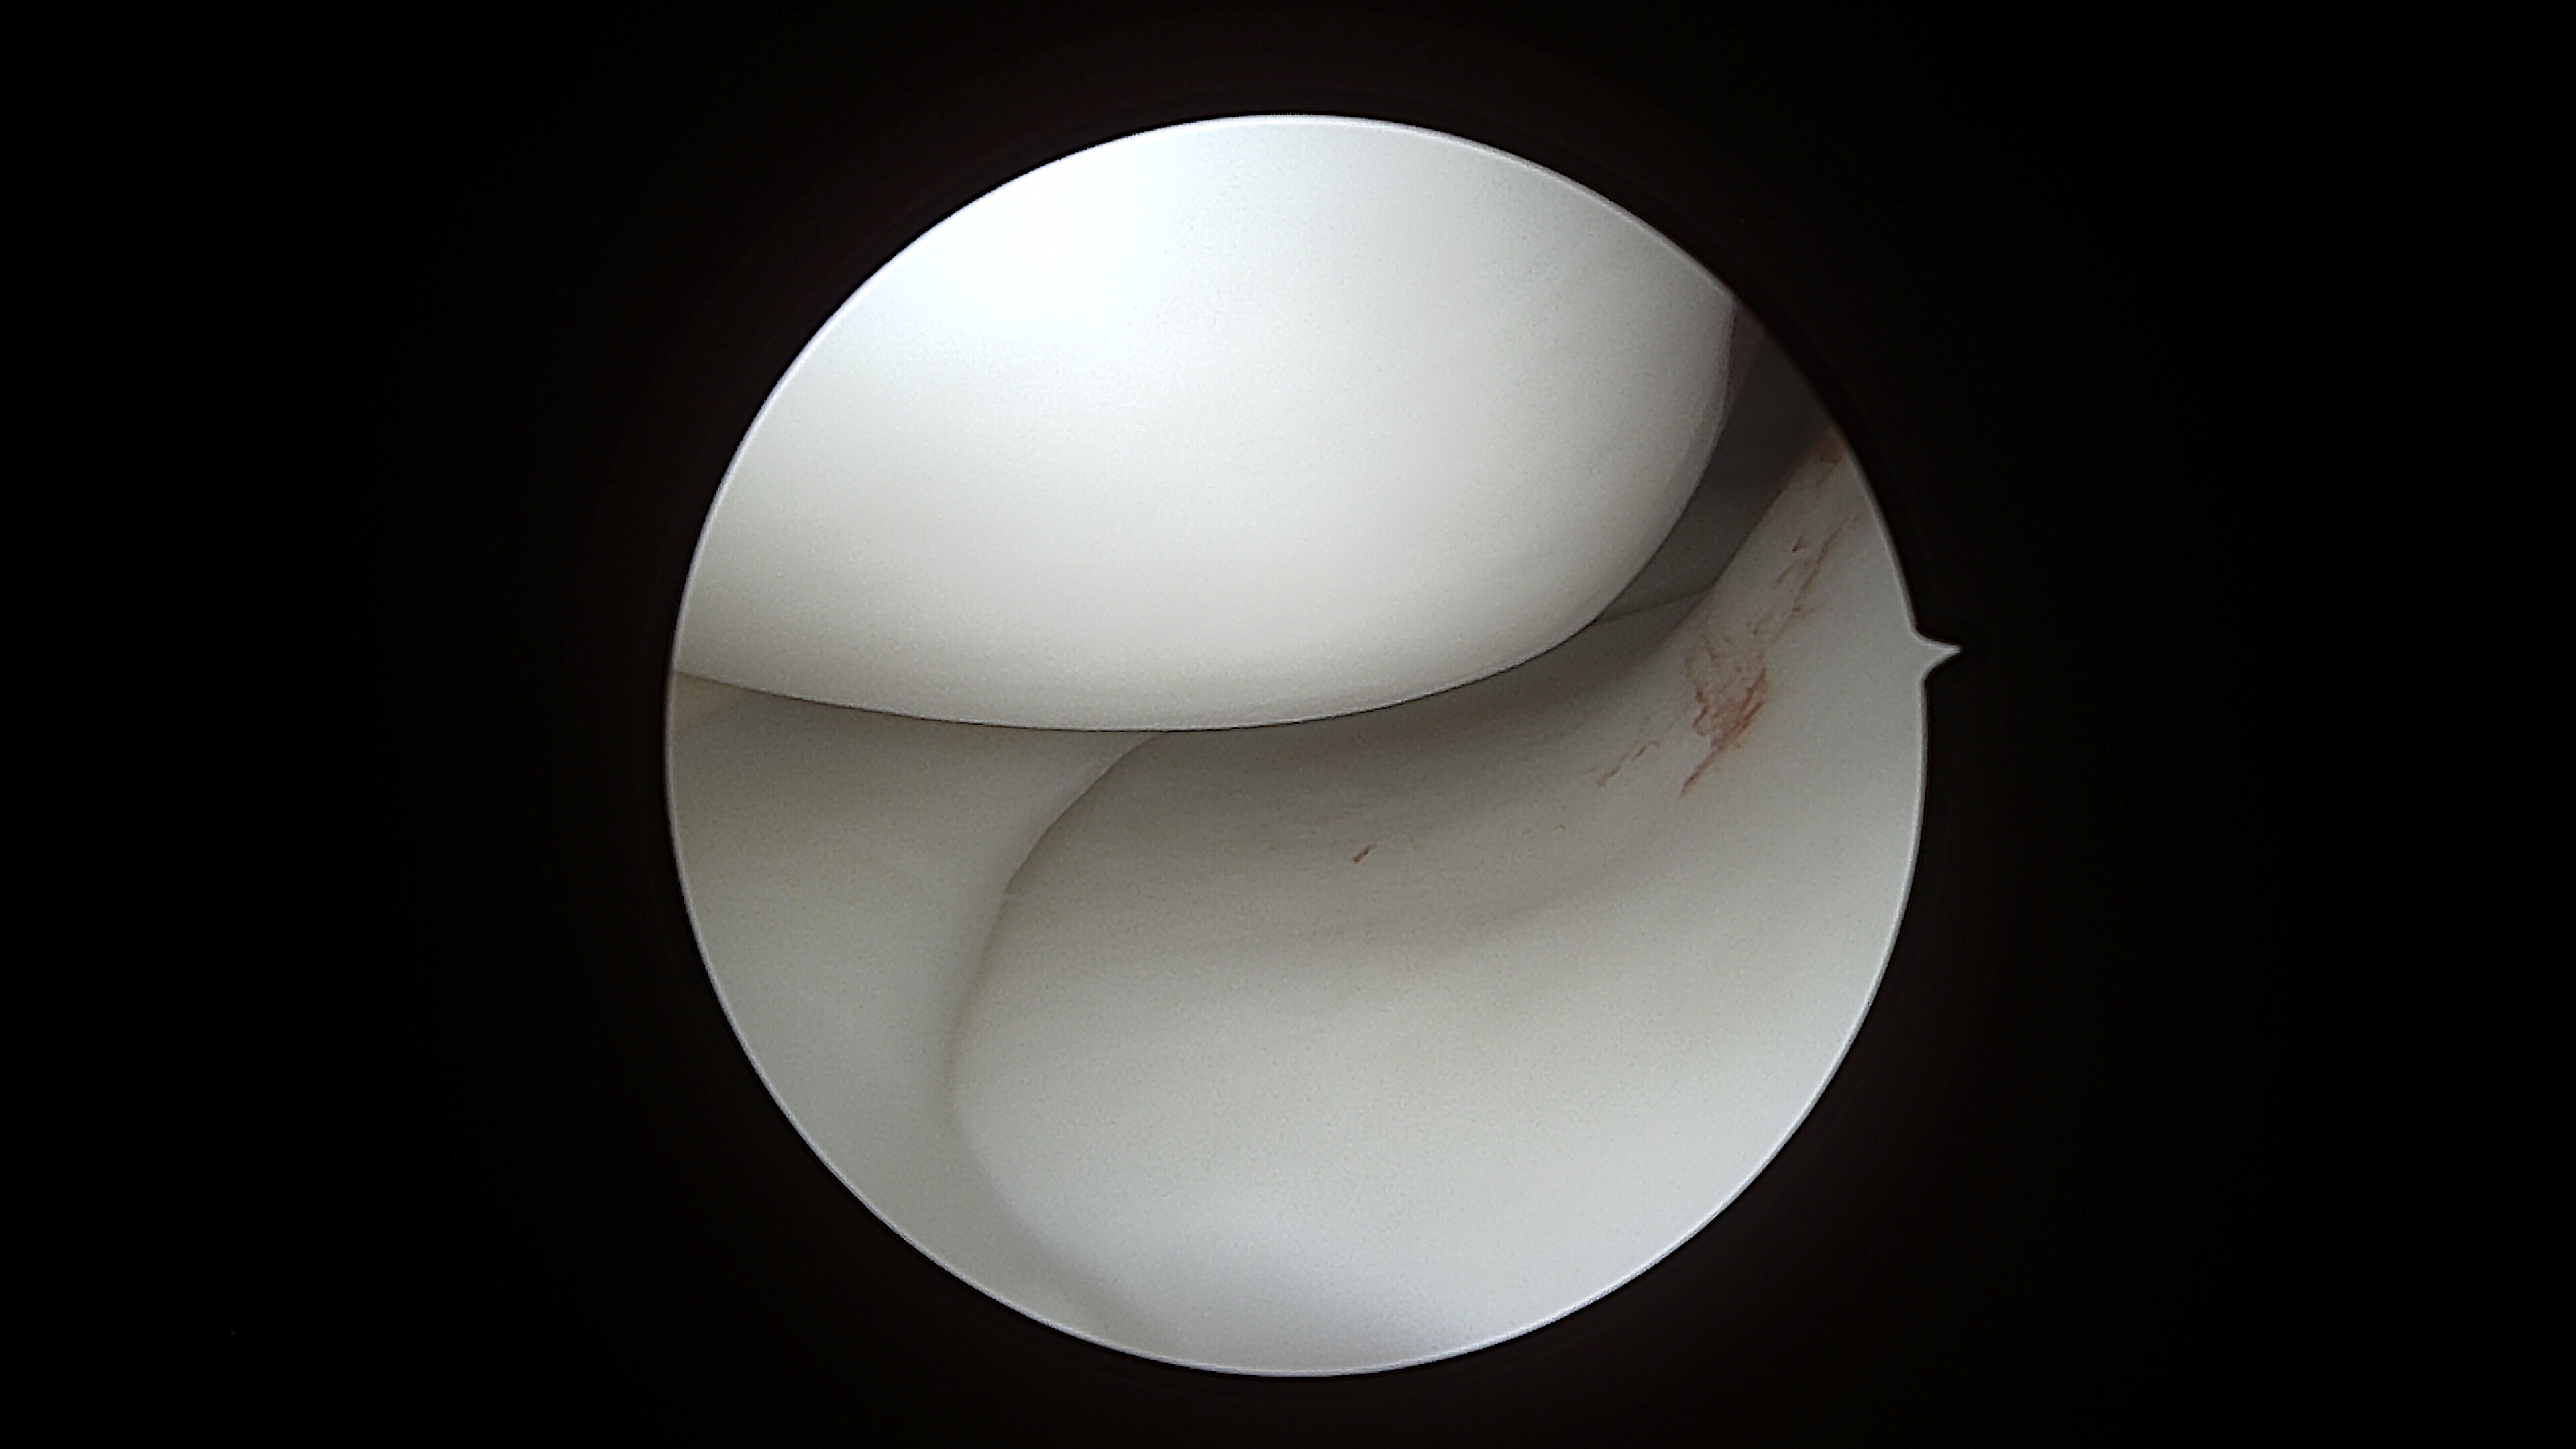

Lesioni meniscali: I menischi svolgono un ruolo essenziale nella protezione dell’articolazione. Una loro lesione può provocare dolore improvviso, blocchi articolari e limitazione funzionale. Attraverso procedure artroscopiche mini-invasive intervengo in modo preciso sulla parte danneggiata, riducendo i tempi di recupero e facilitando il ritorno alle normali attività quotidiane.